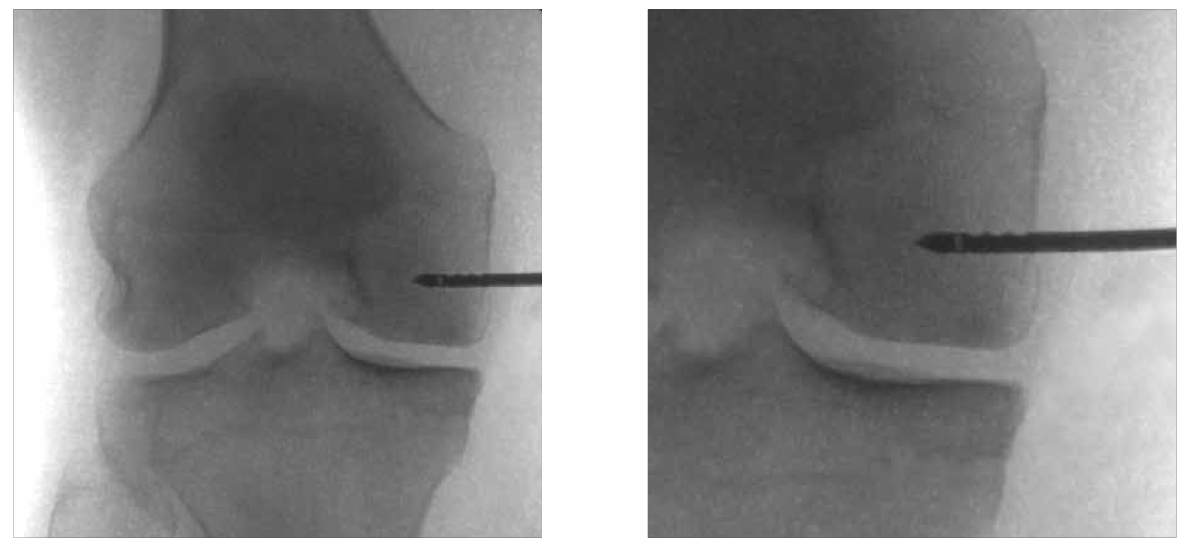

A técnica da subcondroplastia é minimamente invasiva, realizada sob controle fluoroscópico (radioscopia). O procedimento envolve:

- Identificação da lesão óssea medular por fluoroscopia.

- Inserção de uma cânula específica, orientada por radioscopia, diretamente na área da lesão.

- Injeção cuidadosa do fosfato de cálcio sintético na lesão óssea medular.

- Monitorização da distribuição adequada do material durante a aplicação, assegurando o preenchimento uniforme e eficaz da área comprometida.